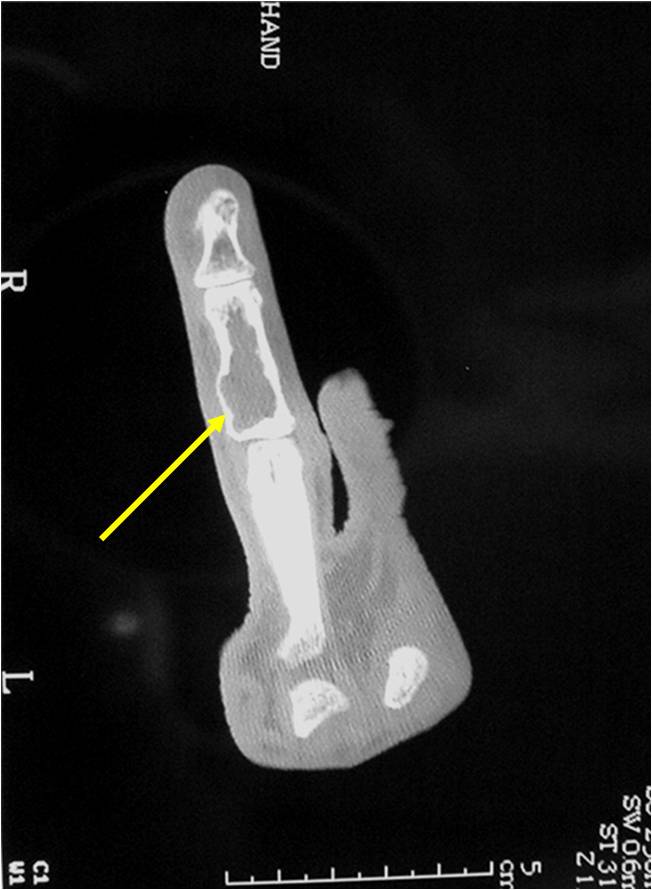

- Features consistent with chondrosarcoma

- Cortical destruction and a soft tissue mass

- Periosteal reaction and thickening

- Endosteal erosion>2/3 cortical thickness on a CT scan

- Size greater than 5 cm

- Endosteal scalloping and cortical expansion is acceptable for phalangeal tumors. In most benign long bone cartilage tumors there is minimal endosteal scalloping but there should be no cortical expansion nor thickening. There should be no cortical destruction and no soft tissue component associated with an enchondroma. Cortical destruction, periosteal thickening, cortical expansion and a soft tissue component indicates a chondrosarcoma of the long bone.

- There should never be any cortical destruction nor a soft tissue component. If this exists then the tumor must be a chondrosarcoma.